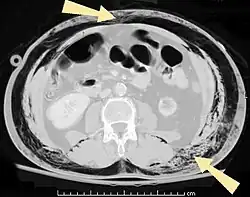

An abdominal CT scan of a patient with subcutaneous emphysema (arrows)